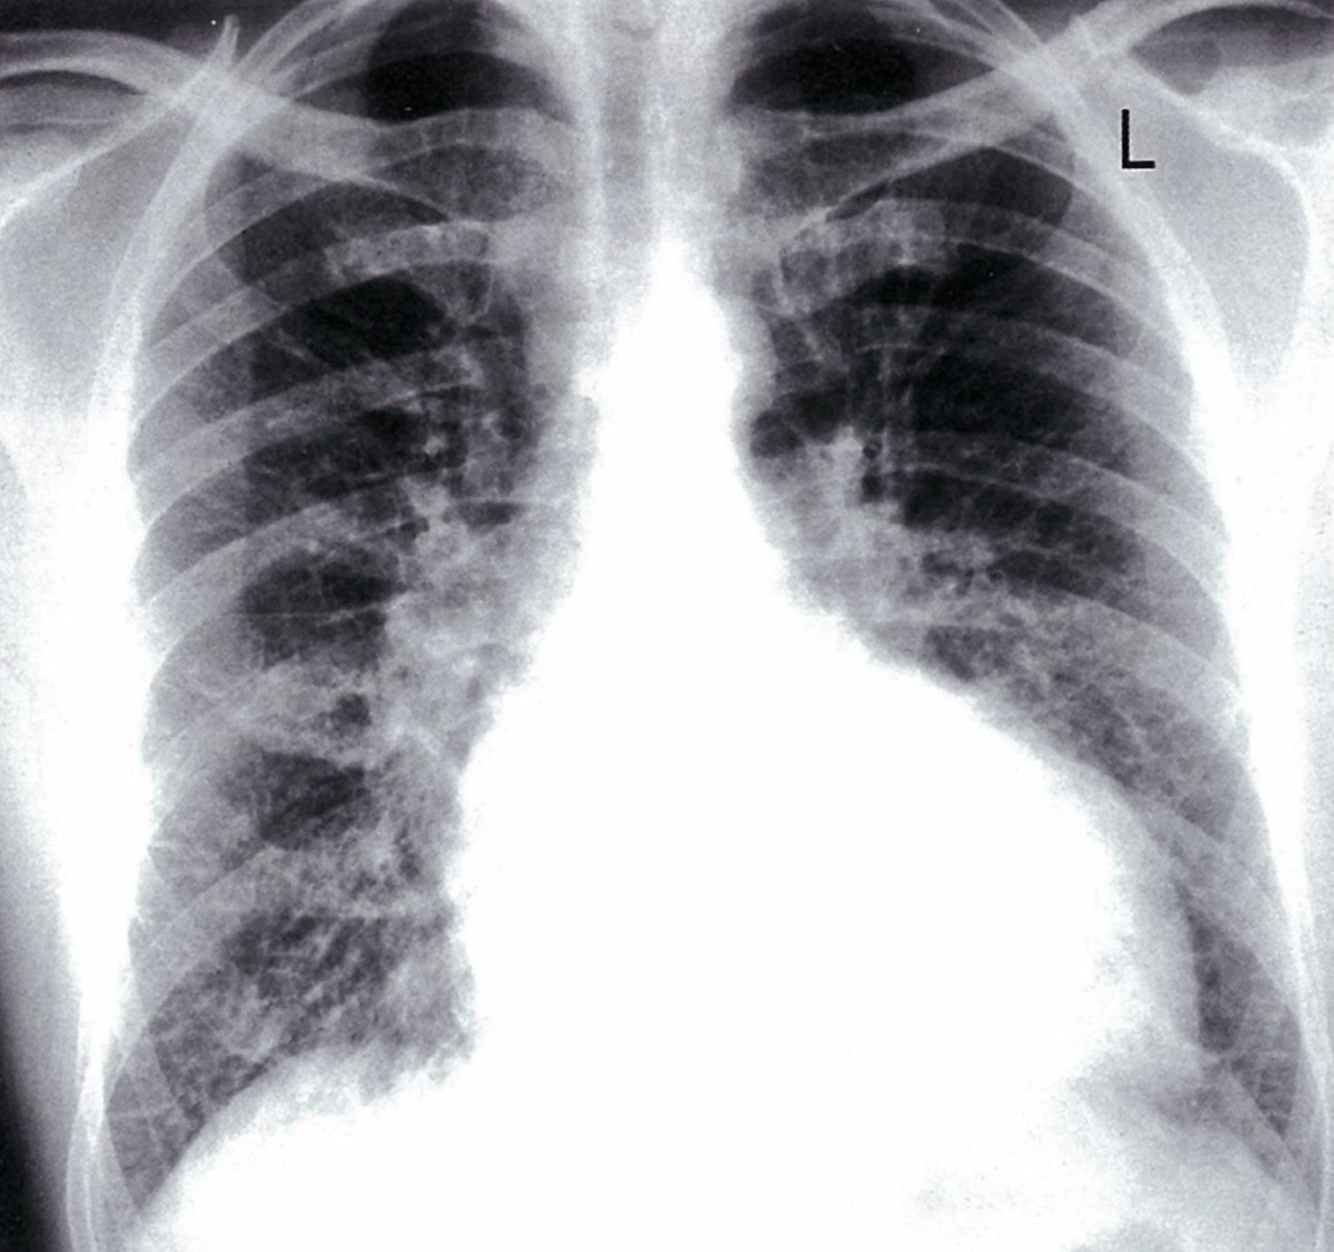

Post-primary tuberculosis

Posteroanterior chest x-ray showing bilateral apical, streaky parenchymal densities (green borders). These are most likely cavernous changes, which may occur during the course of post-primary tuberculosis. The full extent of cavernous formation can not be assessed on an x-ray; a CT scan should be performed.